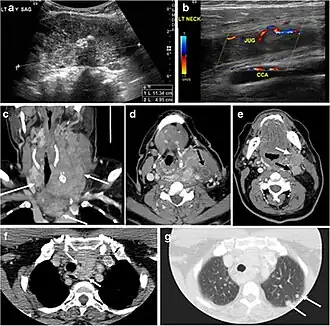

Fig. 4. A 45-year-old male patient presented with anterior mediastinal metastatic PTC lesions and occult primary on imaging. Histopathology examination of the resected thyroid gland revealed micro-foci of PTC; the largest, in the isthmus, measured 4 mm. a transverse greyscale ultrasound of the thyroid demonstrates homogeneous gland with normal echogenicity and size. No focal lesion or micro-calcifications. b Non-enhanced CT scan obtained as part of PET/CT examination shows a heterogeneous, large, relatively dense anterior mediastinal mass (white arrow) with peripheral calcification (arrowheads). Thyroid gland has normal CT appearance with no abnormal FDG uptake (not shown).[1] -

Fig. 6. A 61-year-old female patient with locally aggressive PTC. an Enhanced axial CT scan of the neck demonstrates a heterogeneous infiltrative thyroid mass. This mass diffusely involves the entire gland and circumferentially encases the trachea with involvement of bilateral tracheoesophageal grooves (white arrows). b, c Additional axial cranial images show right cricoid cartilage destruction (black arrows in b), right thyroid cartilage destruction (black arrow in c), right vocal cord paralysis (white arrows in b), and bilateral cervical lymphadenopathy (arrowheads).[1]

Finally, the possibility of metastatic disease should be excluded. PTCs and medullary thyroid carcinomas tend to metastasize to regional lymph nodes. According to the AJCC/UICC TNM staging system, the nodal stage is classified by site: N1a indicates level VI nodal involvement, including paratracheal nodes; N1b indicates unilateral or bilateral lateral cervical nodal disease or superior mediastinal nodal disease (Figs. 4, 55 and and6)6).[1]